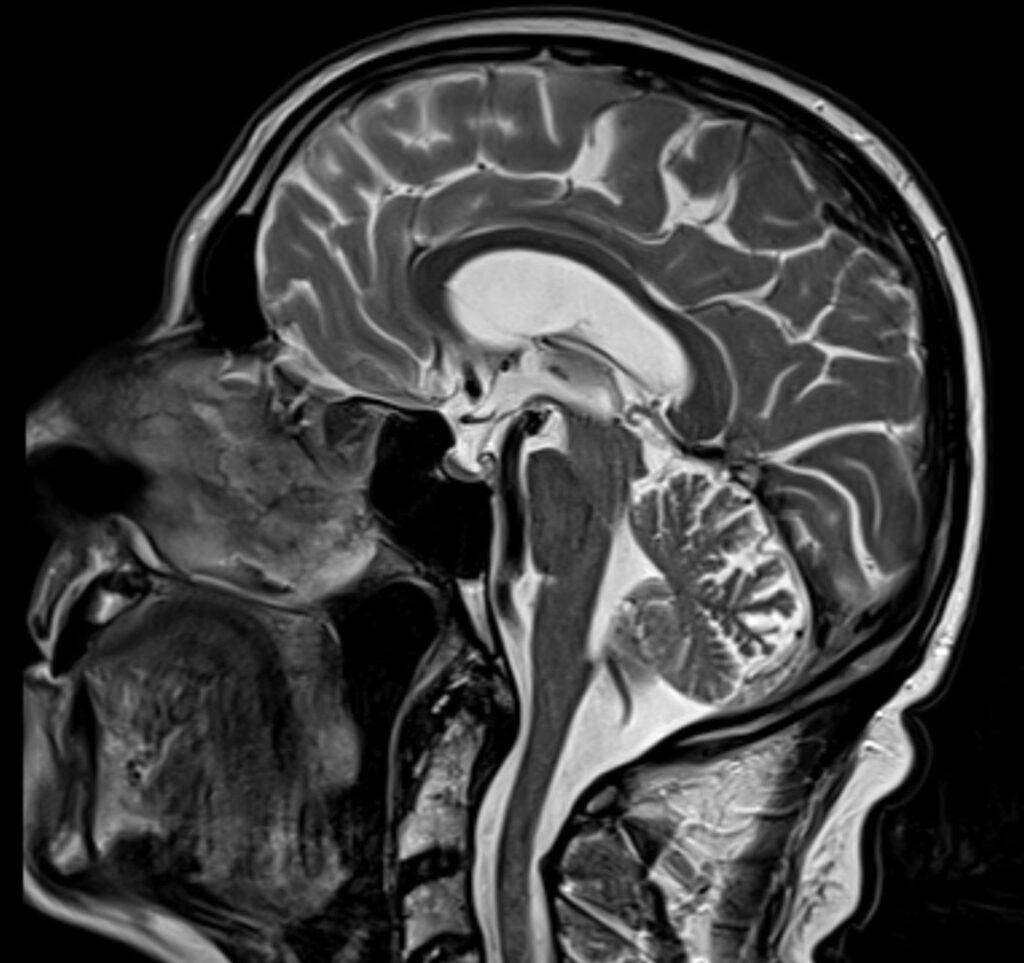

MRT Kopf – was sieht man?

Eine Kopf MRT liefert Ärzte und Radiologen detaillierte Bilder. Zu sehen sind das Gehirn, Schädelknochen, Blutgefäße und anderer umgebende Gewebe im Kopfbereich.

Hirntumor in der MRT